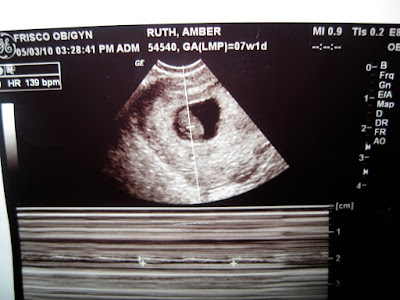

My first prenatal appointment! We did take pictures at the appointment but I dont have them with me to put on here. We had our first sonogram done! Seeing this tiny little hearbeat was the most incredible thing I have ever seen. The heart beat was 139, this makes me think its a boy. Heres the sonogram pics!